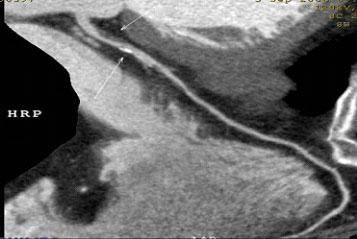

CT冠脈血管成像:

1.冠脈軟斑塊:

2.混合性斑塊:

3.對于斑塊性質的确定,CT優于DSA: